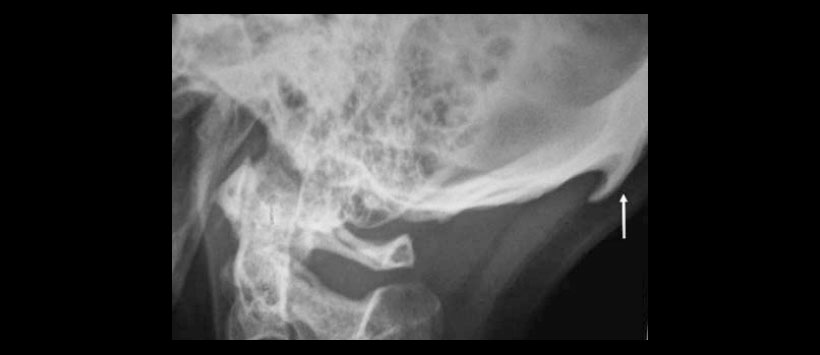

Se solicita radiografía lateral de columna cervical, abarcando cráneo (Figura 1) observando entesofito en la inserción del ligamento nucal a nivel de su inserción occipital (Figura 2).

Se le explica que es una variante normal, que de incrementar sintomatología puede ser resecado. El inión o protuberancia occipital externa es la proyección más prominente del hueso occipital en la parte posteroinferior del cráneo humano, siendo el sitio de inserción del ligamento nucal y el músculo trapecio. Los entesofitos u osteofitos son proyecciones óseas que se observan en sitios de inserción ósea de ligamentos, tendones o cápsula articular, cuando se presentan a nivel de la protuberancia occipital externa se denominan: espolón occipital, perilla occipital, moño occipital o gancho del inión, antropológicamente se les ha relacionado como un rasgo del Neandertal, y se les considera como una variante normal, por lo que pocas veces se reporta radiológicamente.